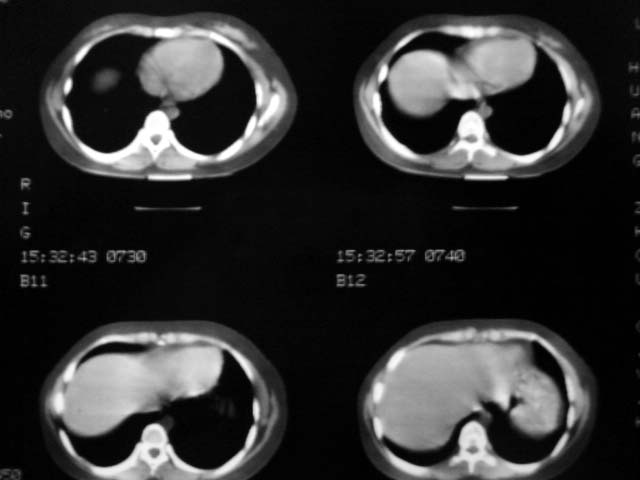

标题: CT12463:女,19岁,炎性假瘤?结核球? [打印本页]

女,19岁,体检时发现。炎性假瘤?结核球?

早产儿,幼时体弱,常感冒肺部感染,13岁后好转。两月前“感冒”后咳嗽两周。

纵隔窗肿块明显较肺窗小,切粗长毛刺,“倒核桃”征:考虑炎性假瘤

病灶肺纵比较大,边缘平直,周围无卫星灶,考虑炎症。建议抗炎治疗后复查。

病灶片状改变,呈钱币样,周围炎性反应明显,考虑球形肺炎可能性大,球形肺炎与炎性假瘤鉴别的重要一点是,炎性假瘤抗炎治疗不会明显改变。

考虑炎症,抗炎后复查。理由:病变肺窗显示的大小明显大于纵隔窗,提示病变周围为密度偏低的渗出改变。不同于结核球和肿瘤。